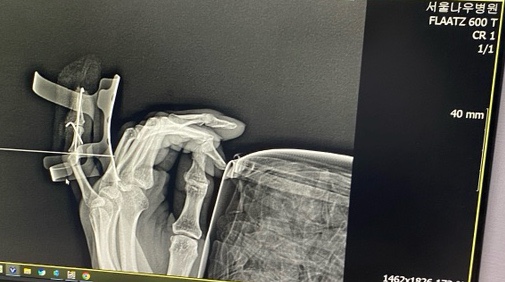

징그러움주의 / 손가락부러진지 10일째

냉장고의 반찬통이 떨어지면서 내 새끼 손가락을 타격한지 10일째 되는날 ! 부러져서 피스를 두개나 박음 !...